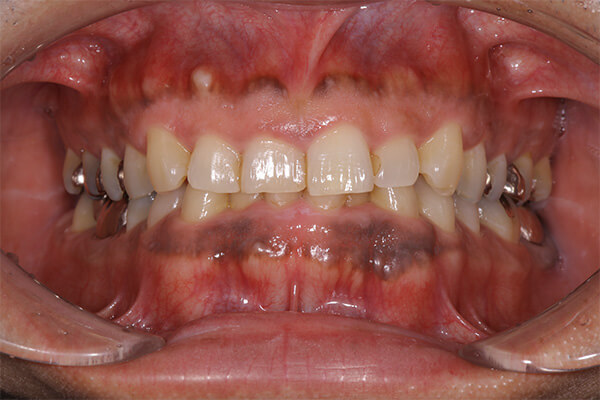

セラミックインレーの装着時には写真のようにラバーダムというゴムのシートを使うことにより接着力が増します。